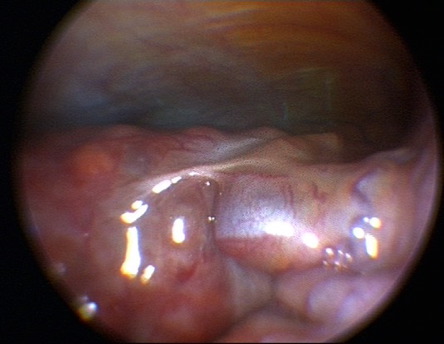

Leberzirrhose mit portaler Hypertonie und rekanalisierter Umbilikalvene